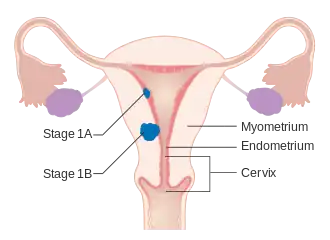

O carcinoma endometrial é estadiado cirurgicamente usando o sistema de estadiamento de cancro FIGO. O sistema de preparação do FIGO de 2009 é o seguinte:[56][57]

| Etapa | Descrição |

|---|---|

| I A | O tumor está confinado ao útero com menos da metade da invasão miometrial |

| IB | O tumor está confinado ao útero com mais da metade da invasão miometrial |

| II | O tumor envolve o útero e o estroma cervical |

| IIIA | O tumor invade a membrana serosa ou anexos |

| IIIB | Envolvimento vaginal e/ou parametrial |

| IIIC1 | Envolvimento do linfonodo pélvico |

| IIIC2 | Envolvimento de linfonodos para-aórticos, com ou sem envolvimento de linfonodos pélvicos |

| IVA | O tumor invade a mucosa da bexiga e/ou mucosa do intestino |

| IVB | Metástases distantes, incluindo metástases abdominais e/ou linfonodos inguinais |

A invasão miometrial e o envolvimento dos linfonodos pélvicos e para-aórticos são os padrões de disseminação observados com maior frequência.[2] Às vezes, é incluído um Estágio 0, neste caso denominado "carcinoma in situ".[9] Em 26% dos cancros presumivelmente em estágio inicial, o estadiamento intraoperatório revelou metástases pélvicas e à distância, tornando necessário um estadiamento cirúrgico abrangente.[25]

Cancro do endométrio em estágio IA e IB

Cancro do endométrio em estágio IA e IB Cancro do endométrio em estágio II